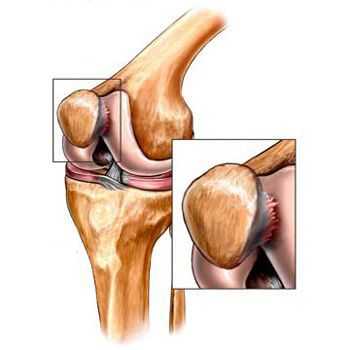

- травмы (переломы, разрыв менисков и передней крестообразной связки). [15][19] К сожалению, у любого человека, независимо от возраста, данные повреждения приводят к излишней нагрузке на хрящ. Перелом любых участков костей, покрытых хрящом, сопровождается образованием неровности — «ступеньки». [26] В этой зоне при движении происходит истирание, и формируется артроз;

Его причиной, как правило, становится подвывих, перелом или латерализация надколенника.